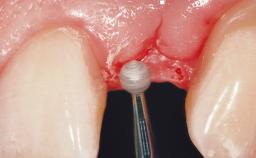

Immediate Flapless Placement of an Implant in a Maxillary Right Lateral Incisor Site

This 43-year-old male patient, a non-smoker, came to our practice because of a fracture of tooth 12 caused by a bicycle accident. Due to the combined para- and infrabony crown and root fracture, tooth extraction, and subsequent implant placement were suggested to the patient as the therapy of choice. The patient had high esthetic expectations with regard to the treatment outcome and asked for an immediate fixed provisional restoration. His individual esthetic risk profile summed up to a medium esthetic risk.

Placement Protocol Immediate implant placement

Tooth Site Maxillary incisor or canine

Socket Morphology Single-root socket

Socket Integrity Sufficient, with intact bone walls